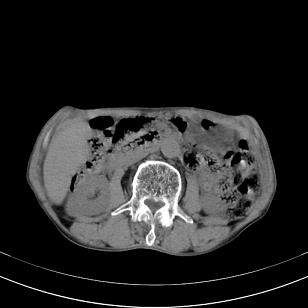

标题: 男,65岁,反复右上腹痛, [打印本页]

标题: 男,65岁,反复右上腹痛,

胃镜提示十二指肠占位